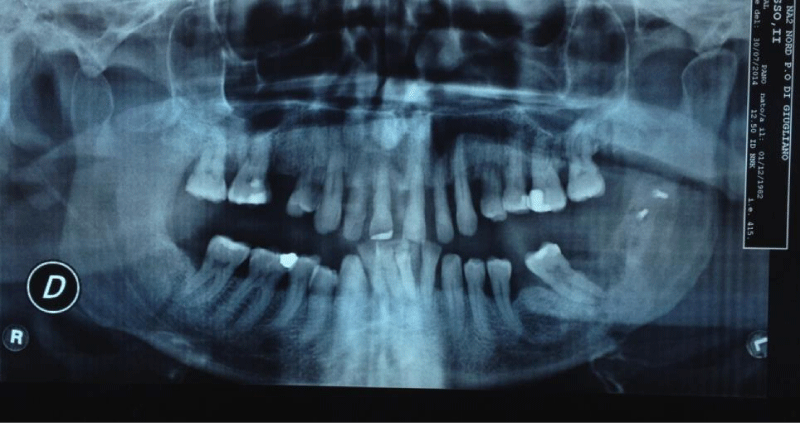

Figure 4:

Orthopantomogram revealing osteolytic area and absence of coronoid-supporting fragment.